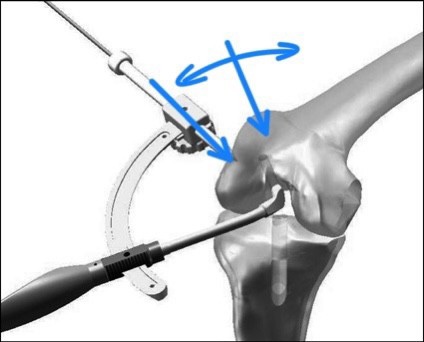

- 전내측 삽입구 술기 (AM portal technique)

경경골 술기를 통해 해부학적 위치를 정확하게

복원하기 어렵기 때문에, 이를 해결하기 위해 나온 방법이

전내측 삽입구 술기입니다.

경골 터널을 통하지 않기 때문에, 전내측 삽입구를 통해

전방십자인대가 무릎에 붙는 해부학적 위치에서 터널을

뚫을 수 있습니다.

-전내측 삽입구 술기의 단점

다만 문제는, 이렇게 전내측 삽입구를 통해서

터널을 뚫게 되면, 시작점은 해부학적인 위치에

잡을 수 있지만, 무릎뼈 자체의 모양때문에

터널의 방향에는 제한이 걸리게 되는데,

이 때문에 전내측 삽입구 술기에서는

대퇴 터널의 길이가 다른 방법에 비해

가장 짧아집니다.

문제는 터널의 길이가 짧아지는 만큼, 터널을 통과하는

인대가 터널 안에 접촉하는 면적이 좁아지기 때문에

인대의 안정성이 떨어진다는 단점도 있습니다.

- Outside-in 술기

전내측 삽입구 술기의 장점을(해부학적 터널 시작점)

살리면서도, 단점(터널이 짧아짐)을 해결하기 위해

특수하게 제작된 가이드를 사용하여,

바깥에서 안으로 터널을 만드는 방법이 고안되어

최근에는 가장 해부학적이고 안정적인 터널 길이를

확보할 수 있는 outside-in 술기가 많이 사용됩니다.